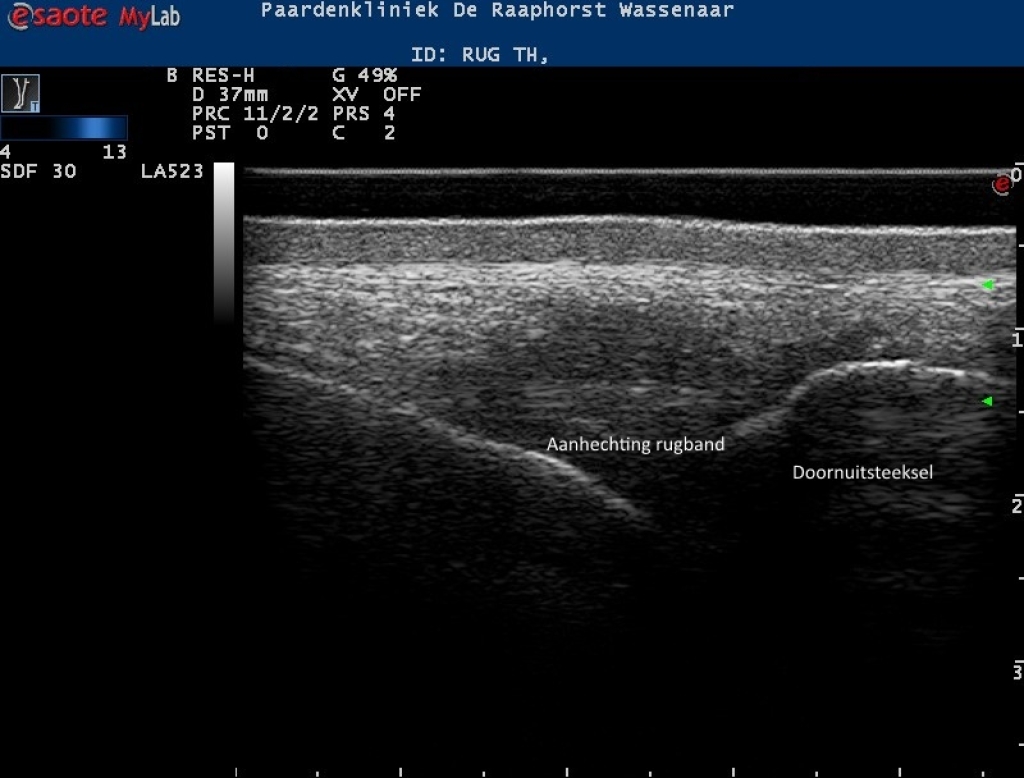

Rechts: Echobeeld van de rugband boven een doornuitsteeksel

Echobeeld van de rugband boven een doornuitsteeksel

Echobeelden van de lengte en dwarsdoorsnede van de rugband

Foto: Echobeelden van de lengte en dwarsdoorsnede van de rugband